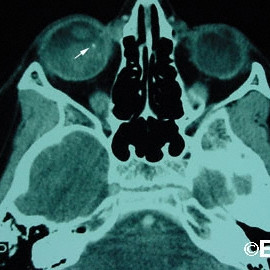

Retinoblastoma

Retinoblastoma - Computed radiographic tomography demonstrates calcium (arrow) within a large intraocular retinoblastoma